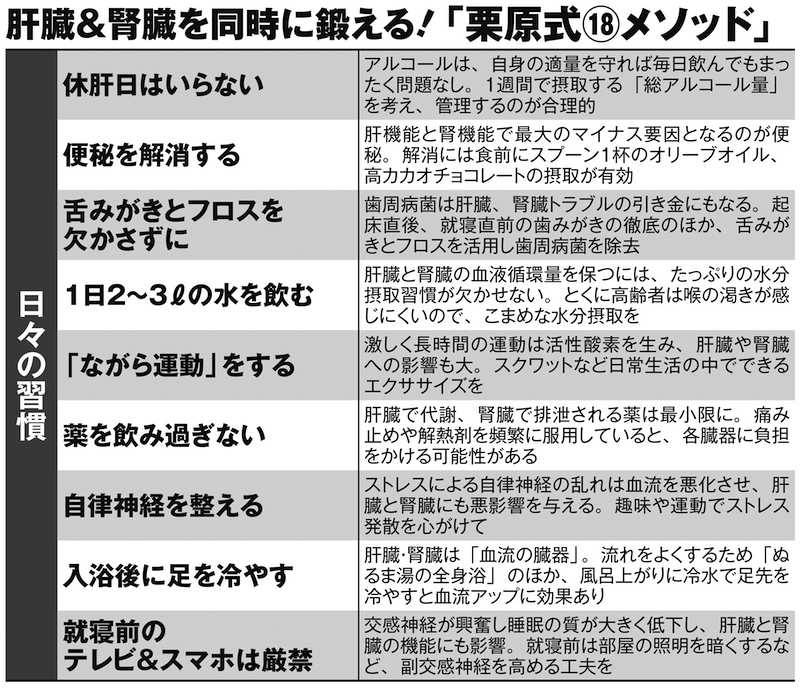

健康